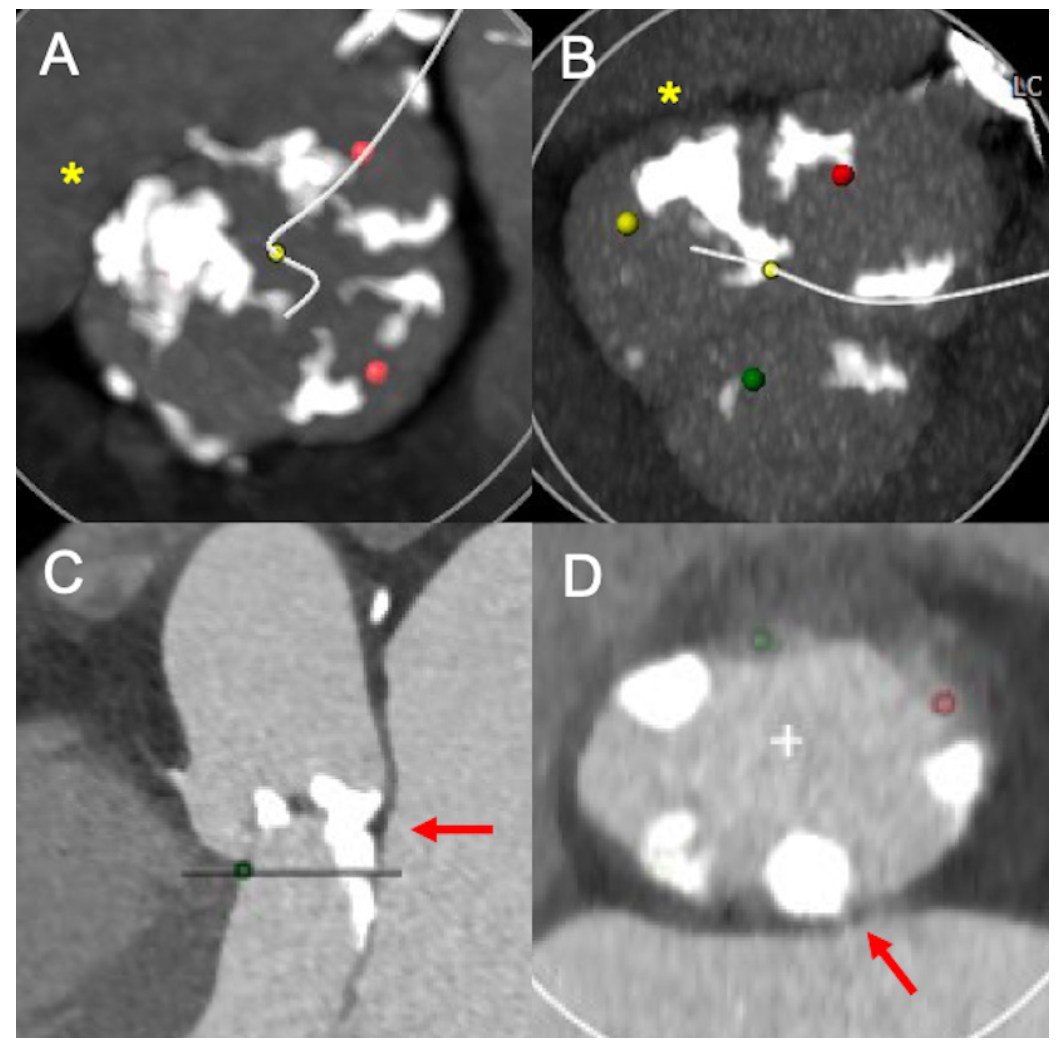

The aortic valve calcium score (AVCS) was measured according to the Agatston method using non-contrast-enhanced MDCT scans.9 The calcium density was calculated as AVCS/annular area (AU/cm2).10 The presence of eccentric aortic valve (AV) calcification and relevant left ventricular outflow tract (LVOT) calcification was determined by visual evaluation of the AV in short-axis views and maximum-intensity projections (Figure 1).11